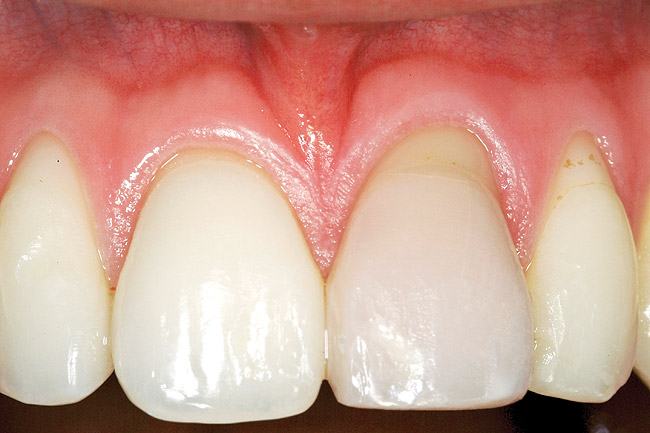

Figure 20 shows the completed view with the final restoration seated. Observe the balance of the facial heights of contour between the central incisors, and the presence of a thick-biotype, attached keratinized tissue.

Figure 20  Case Two Case Two, complete view.

Figure 20